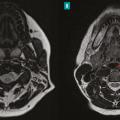

Pour les pathologies inflammatoires, le diagnostic est histologique (réalisation d’une biopsie des glandes salivaires accessoires) lorsqu'est évoqué le diagnostic de syndrome de Sjögren, de sarcoïdose ou de maladie à immunoglobulines G4. Le bilan diagnostique des pathologies tumorales est de plus en plus précis grâce à certaines séquences d’IRM et à la cytoponction à l’aiguille fine. La prise en charge, essentiellement chirurgicale, permet un diagnostic histologique définitif et un traitement curatif.

Les tumeurs des glandes salivaires représentent un groupe hétérogène de lésions, bénignes ou malignes, pouvant atteindre toutes les glandes. Elles regroupent un grand nombre d’histologies différentes : plus de 20 types de tumeurs malignes et plus de 10 types de tumeurs épithéliales bénignes sont recensées dans la dernière…